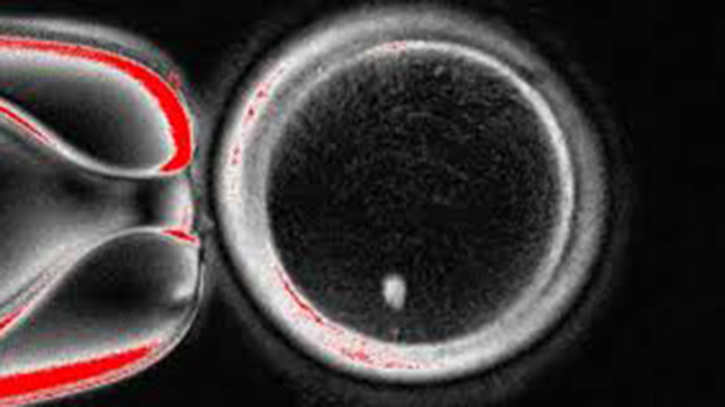

যুক্তরাষ্ট্রের বিজ্ঞানীরা প্রথমবারের মতো মানুষের ত্বকের কোষ থেকে নেওয়া ডিএনএ ব্যবহার করে প্রাথমিক স্তরের মানব ভ্রূণ তৈরি করতে সক্ষম হয়েছেন এবং সেটিকে শুক্রাণুর মাধ্যমে নিষিক্ত করেছেন।

ওরেগন হেলথ অ্যান্ড সায়েন্স ইউনিভার্সিটির (ওএইচএসইউ) গবেষণা দল ত্বকের কোষের নিউক্লিয়াস (যেখানে সম্পূর্ণ জেনেটিক কোড থাকে) সংগ্রহ করে সেটিকে এক দাতা ডিম্বাণুর ভেতরে স্থাপন করেছেন, যে ডিম্বাণুর নিজস্ব জেনেটিক তথ্য মুছে ফেলা হয়েছিল।

এখন পর্যন্ত প্রক্রিয়াটি ডলি নামের ভেড়ি তৈরির (১৯৯৬ সালে প্রথম ক্লোন স্তন্যপায়ী) প্রযুক্তির মতো। তবে এখানে সমস্যা হলো, ডিম্বাণুর মধ্যে ইতোমধ্যেই পূর্ণ ৪৬টি ক্রোমোজোম থাকে। নতুন নিউক্লিয়াস যোগ করার পর এটিকে আবার "সাধারণ ডিম্বাণু"র মতো আচরণ করাতে বিজ্ঞানীরা তৈরি করেছেন নতুন একটি প্রক্রিয়া— মাইটো-মিয়োসিস। এতে ডিম্বাণু নিজের অর্ধেক ক্রোমোজোম ফেলে দেয়, যেন মানুষের প্রজননের মতো ২৩+২৩ ক্রোমোজোমে মিলন ঘটে।

এইভাবে ৮২টি কার্যকর ডিম্বাণু তৈরি করা সম্ভব হয়েছে। এগুলোকে শুক্রাণুর মাধ্যমে নিষিক্ত করা হলে কিছু ভ্রূণ প্রাথমিক স্তর পর্যন্ত গঠিত হয়েছে, যদিও কোনোটিই ছয় দিনের বেশি বাড়তে দেওয়া হয়নি।